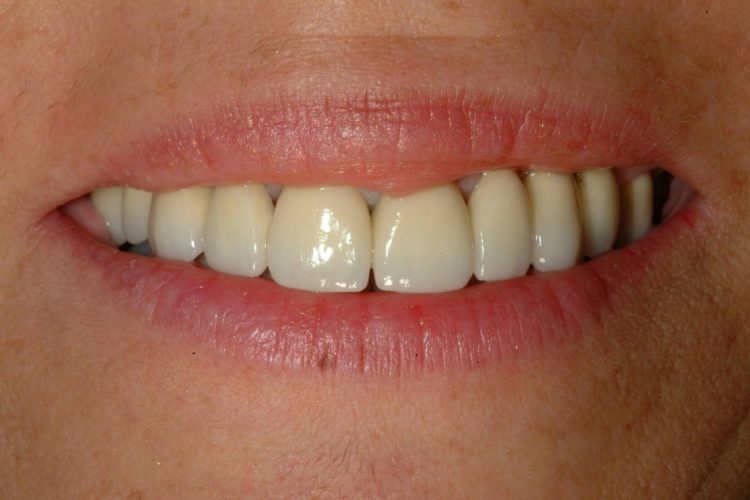

Caso Clínico:  Reabilitação total bimaxilar com 10 implantes e 2 próteses híbridas Descrição: Paciente com 65 anos residente em Macau que pretende uma reabilitação total com implantes no prazo máximo de 8 meses. O tratamento constituíu na extração de todas as peças dentárias, colocação de 6 implantes no maxilar superior e 4 no maxilar inferior culminando